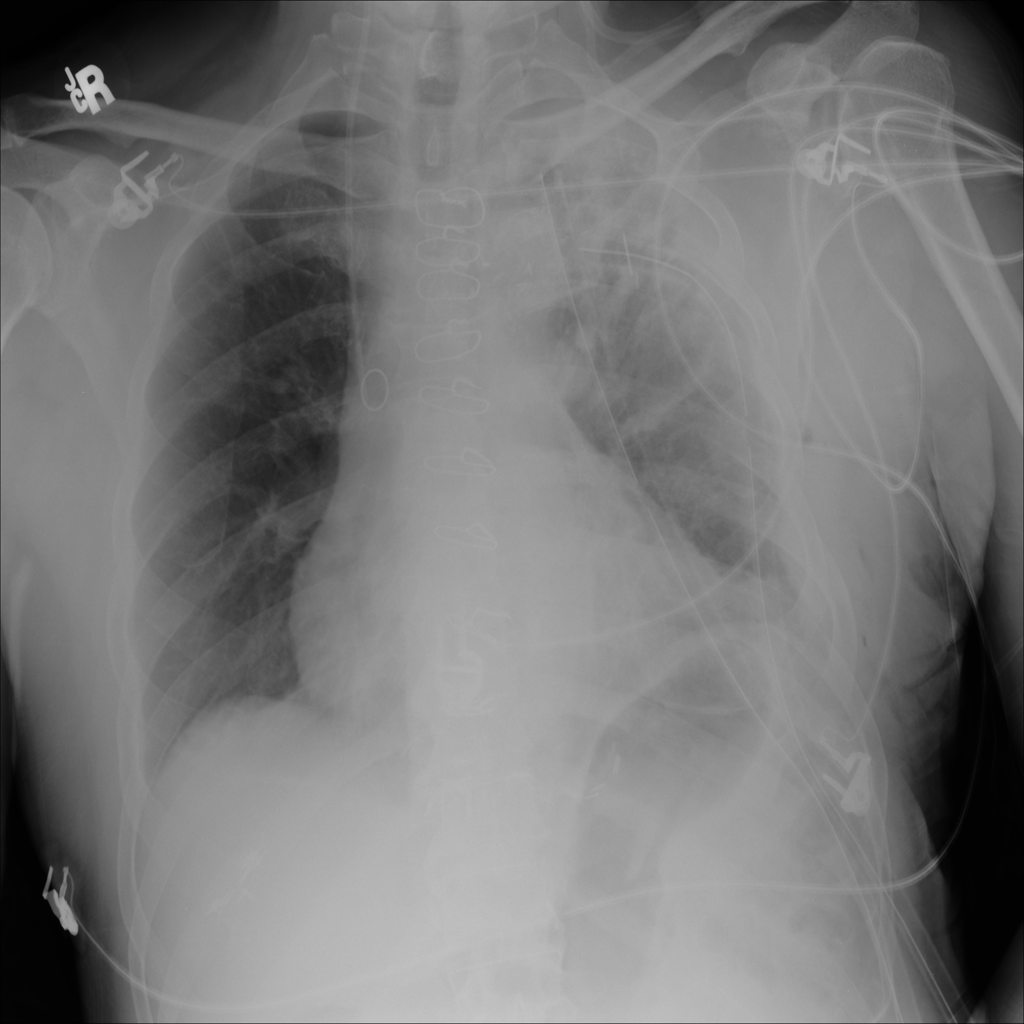

PAT-B0DB · IMG-003Emphysema

PAT-B0DB · IMG-003

PA